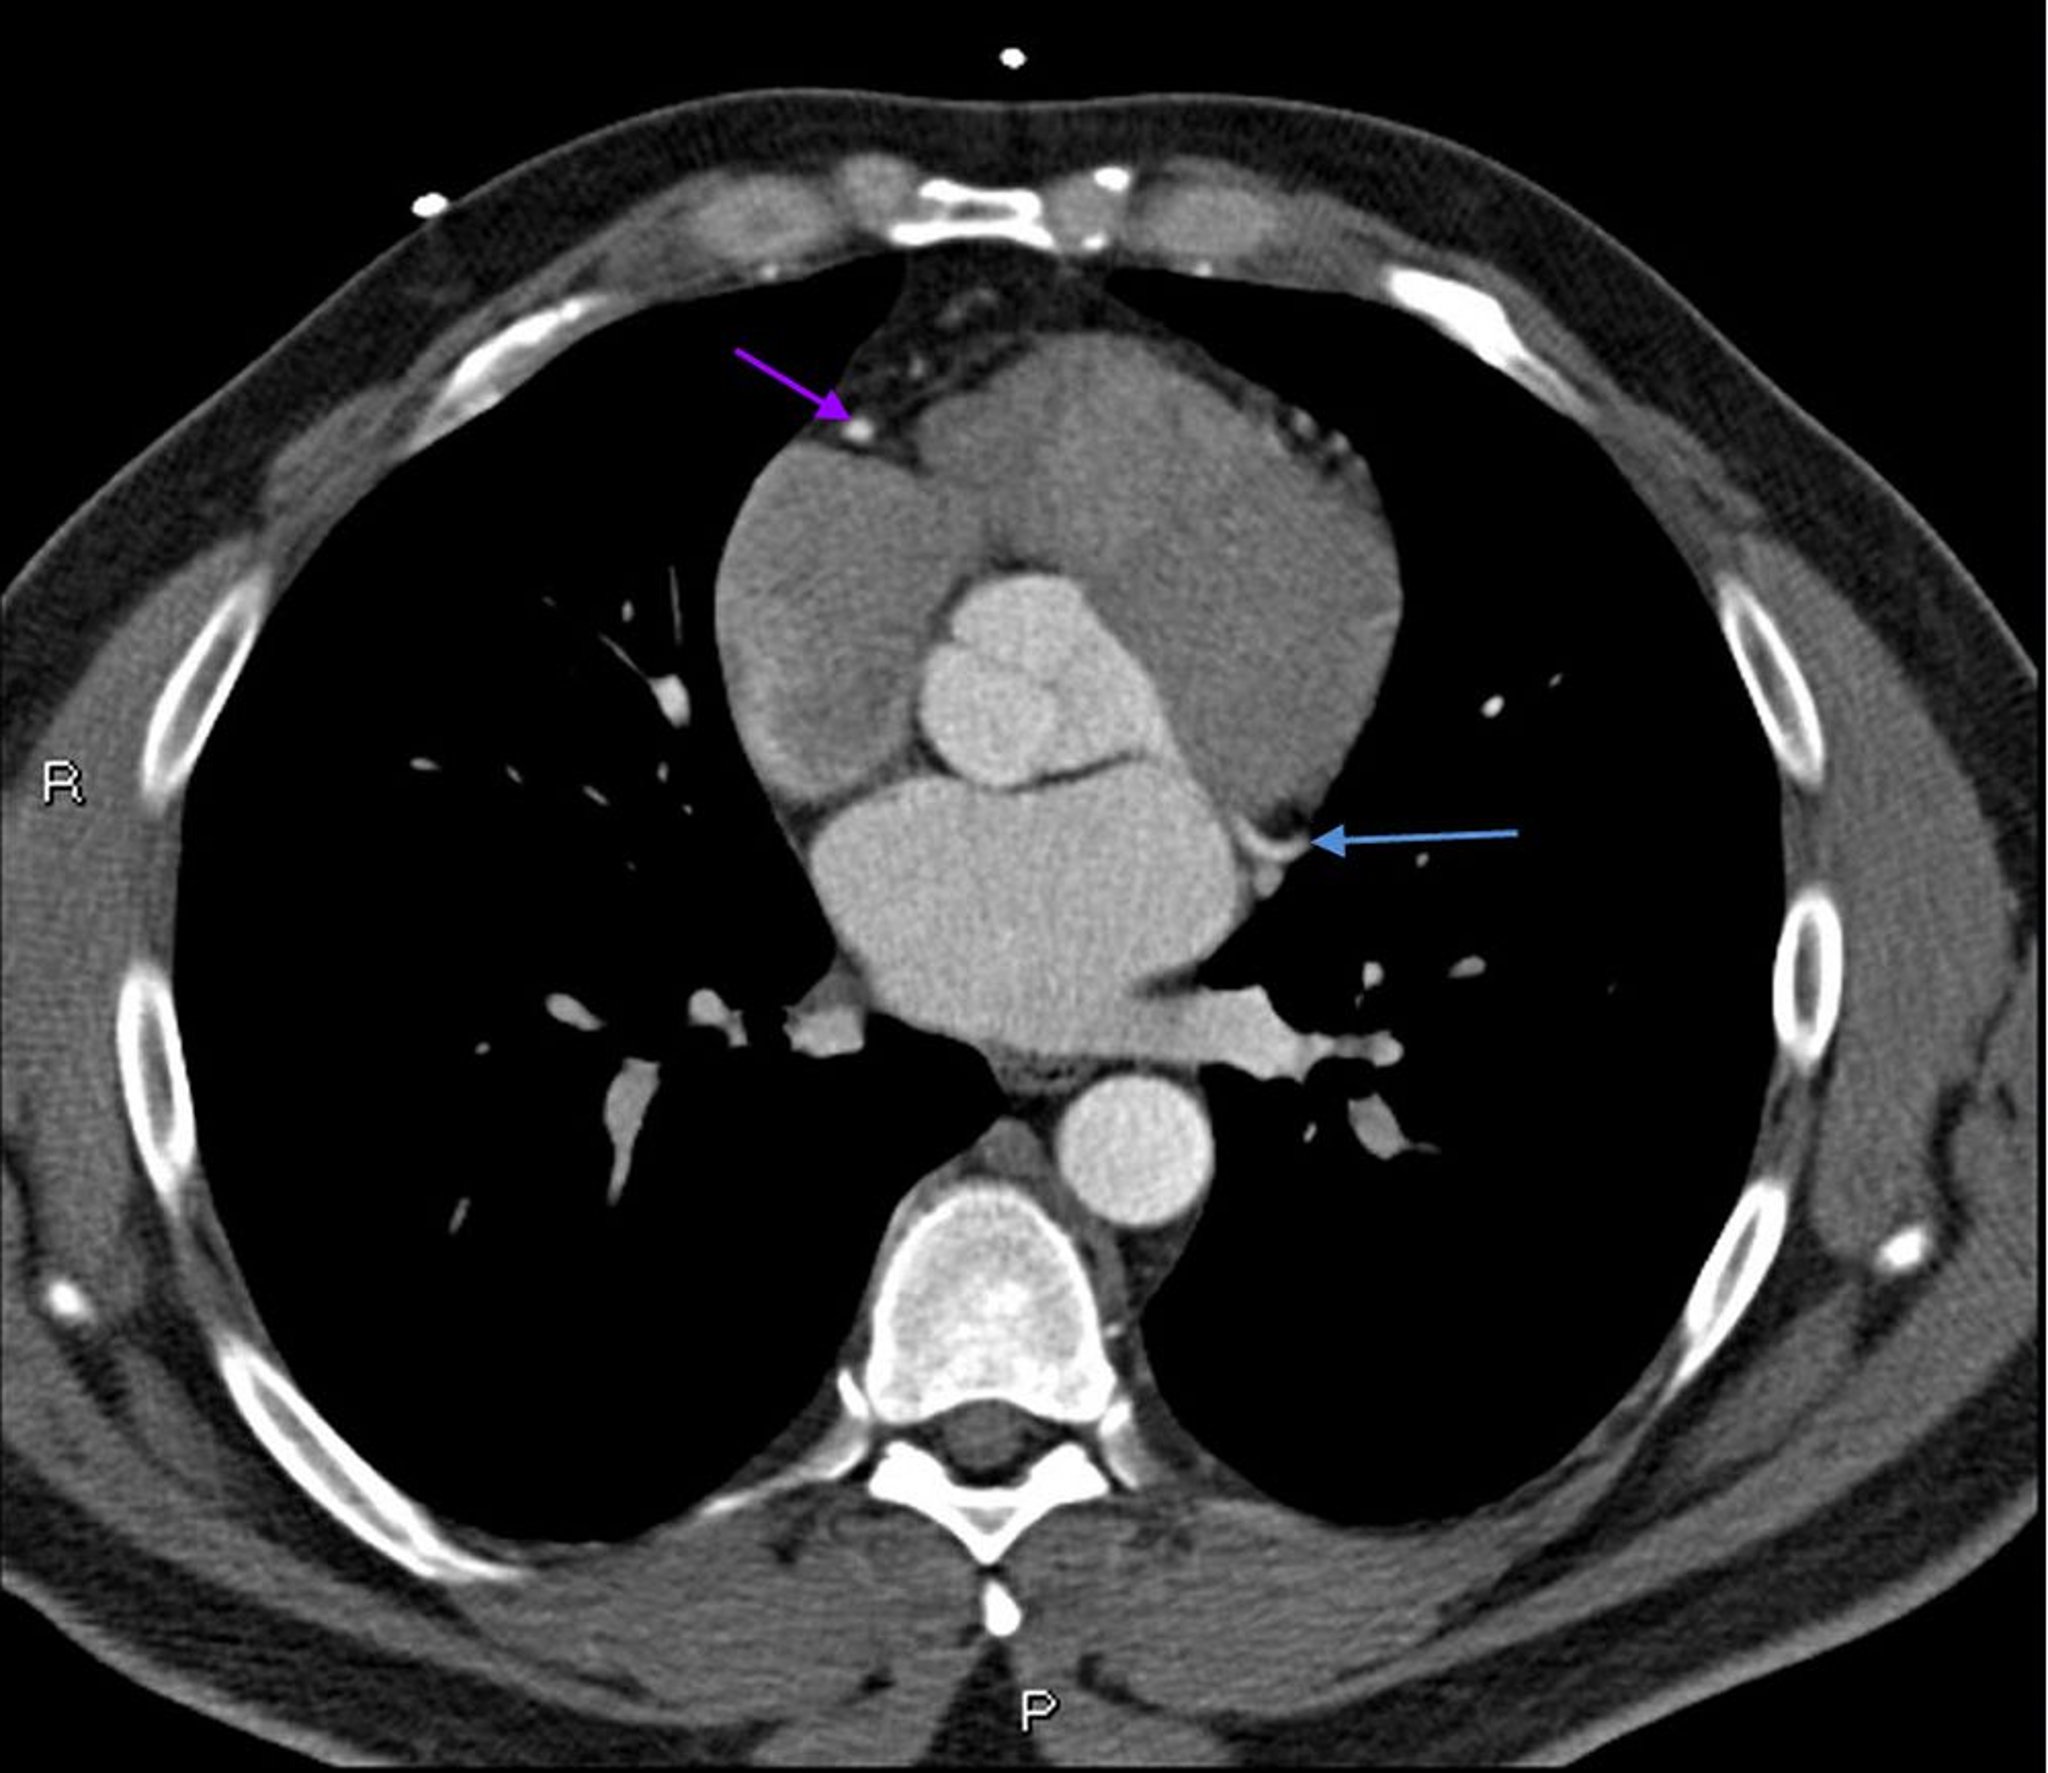

TC con contrasto che mostra arterie coronarie normali, slide 6

Questa TC con contrasto mostra arterie coronarie normali. L'arteria coronaria principale sinistra è indicata dalla freccia rossa. Le arterie discendente anteriore sinistra e circonflessa sinistra sono indicate rispettivamente dalle frecce verde e blu e l'arteria coronaria destra è indicata dalla freccia viola.